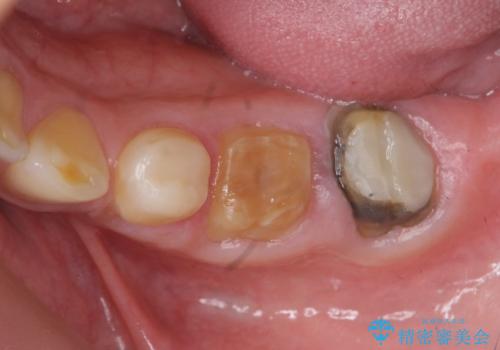

このままの状態でクラウンのやりかえを行うと高さが低く安定の悪いクラウンとなってしまうため、事前に歯周外科手術を行い歯ぐきを下げることで安定性の高いクラウンを製作する治療計画としました。

高さの低いクラウンはセメントが漏出しやすく脱離しやすいだけでなく虫歯の再発の可能性も高まってしまいます。

長期にわたりに安定した環境に整えることで、長く使える可能性を高めることができます。